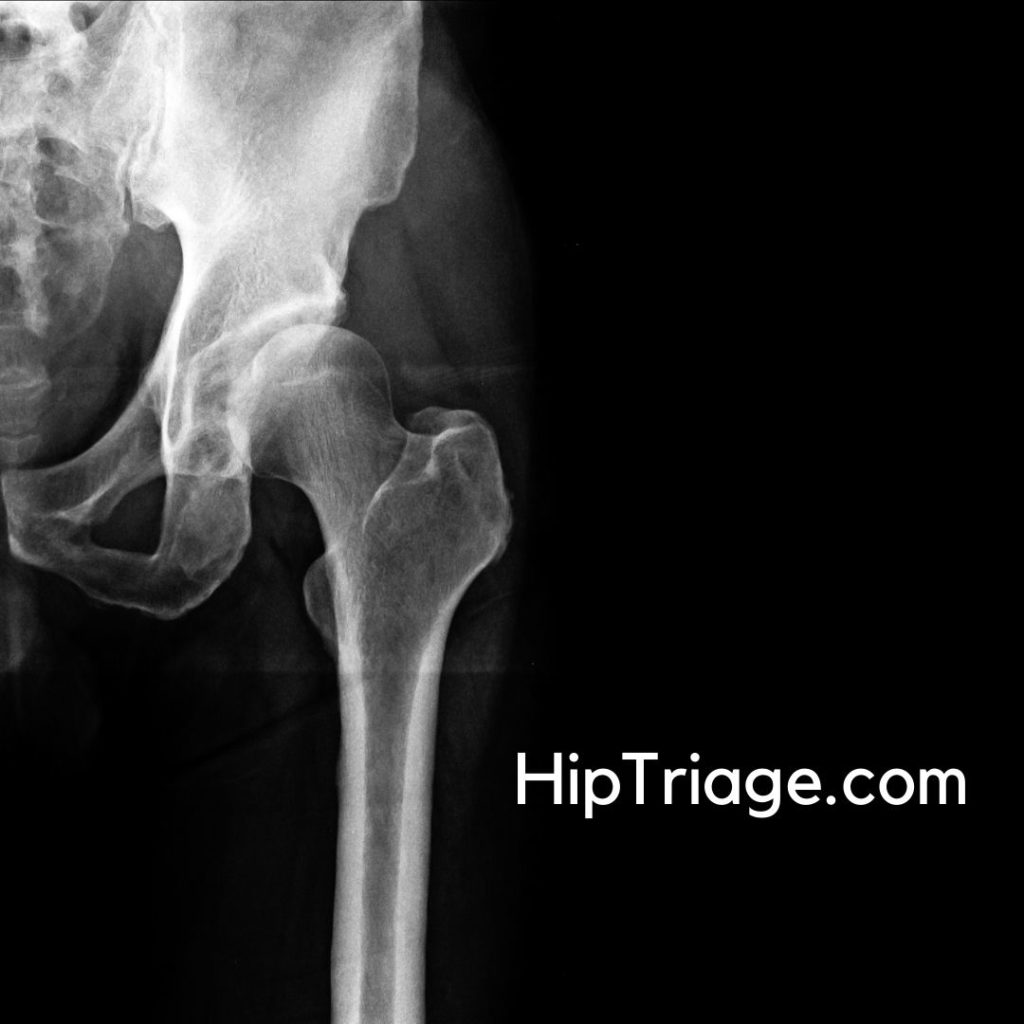

1. Hip Fractures

Hip fractures are common in elderly individuals due to falls and in young individuals due to high-energy trauma.

Types of Hip Fractures

- Femoral Neck Fractures: Located within the capsule; risk of avascular necrosis due to disrupted blood supply.

- Intertrochanteric Fractures: Occur between the greater and lesser trochanters; usually have a good blood supply.

- Subtrochanteric Fractures: Extend below the lesser trochanter; require more complex fixation.

Triage and Management of Hip Fractures

- Stable patients: Urgent orthopedic consultation and imaging (X-ray, CT scan if needed).

- Unstable patients with suspected bleeding: Immediate resuscitation, stabilization, and surgical planning.

- X-rays: First-line imaging for fractures and dislocations.

- CT Scan: Useful for complex fractures and preoperative planning.